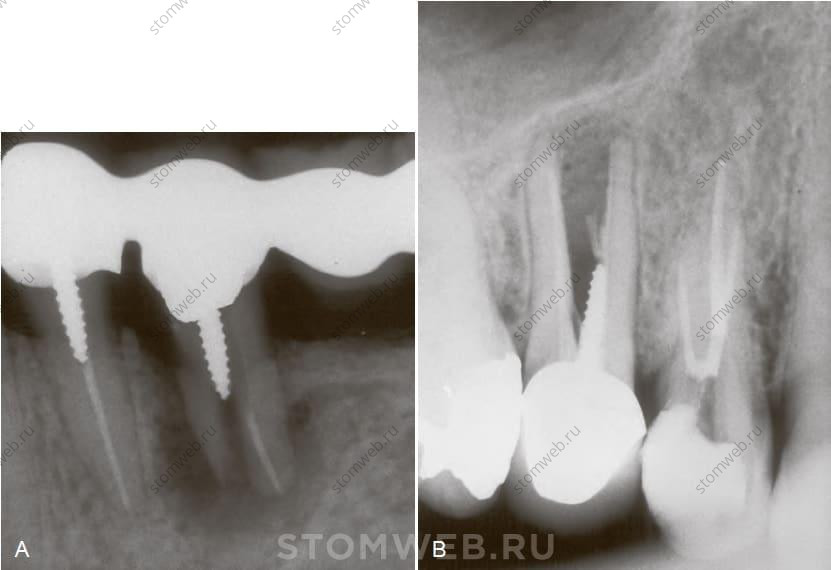

Одной из особенностей КЛКТ является возможность получить изображение зуба и прилежащей костной ткани в вертикальной плоскости. Вертикальные срезы могут предоставить подробную информацию относительно состояния зуба и окружающей его кости (рис. 21-23). Для доступных сегодня КЛКТ устройств ширина переломов без разъединения фрагментов может быть слишком мала и неразличима (см. рис. 21-23). Прицельные рентгенограммы также не слишком помогают при ранней диагностике вертикальных переломов корня. Точнее, деструкция кости или разъединение фрагментов становятся заметны только на более поздних стадиях. Некоторые исследования показали, что обнаружение вертикального перелома корня ранней стадии возможно на вертикальных срезах КЛКТ. Однако возможность обнаружения в значительной степени будет зависеть от разрешающей способности устройства (размер вокселя). При величине вокселя 0,3 мм обнаружение раннего, вертикального перелома корня без смещения маловероятно; при меньшем размере вокселя вероятность обнаружения значительно возрастает. Хотя считается, что размер обнаруживаемой трещины должен быть в два раза больше размера вокселя, документально данная теория не подтверждена. Таким образом, при наименьшем размере вокселя в доступных на сегодняшний день устройствах для КЛКТ 0,075 мм такое устройство обнаружит трещину корня только если она будет шире 0,15 мм. Также следует отметить, что наличие в канале гуттаперчи или металлического штифта часто приводит к появлению артефактов, которые очень сложно отличить от вертикального перелома корня.

РИС 21-23 «Невидимая» костная деструкция при вертикальном переломе корня. А) Вертикальный перелом щечной поверхности медиального корня первого левого нижнего моляра. На ранней стадии уже обнаружен типичный для вертикального перелома корня карман, однако сопутствующей деструкции кости на прицельной рентгенограмме не видно. Зато ее хорошо видно на вертикальном срезе КЛКТ. В) Вертикальный перелом небной поверхности щечного корня первого верхнего премоляра. Присутствует свищевой ход с отделяемым без каких либо признаков поражения на рентгенограмме. С) На КЛКТ обнаружен очаг просветления костной ткани с небной стороны щечного корня, который, как выяснилось после удаления зуба, явился следствием вертикального перелома корня. Заметьте, что ни в одном из представленных случаев линия перелома не была заметна на КЛКТ.

Хотя раннее обнаружение вертикального перелома корня все еще не под силу современным устройствам КЛКТ, ранняя деструкция костной ткани возле подозреваемого перелома вполне может быть заметна на вертикальных срезах, когда она еще не видна на прицельных снимках; Такие обнаруженные очаги деструкции могут помочь установить диагноз вертикальный перелом корня (см. рис. 21-23).